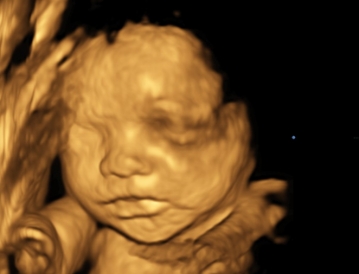

Cara 2